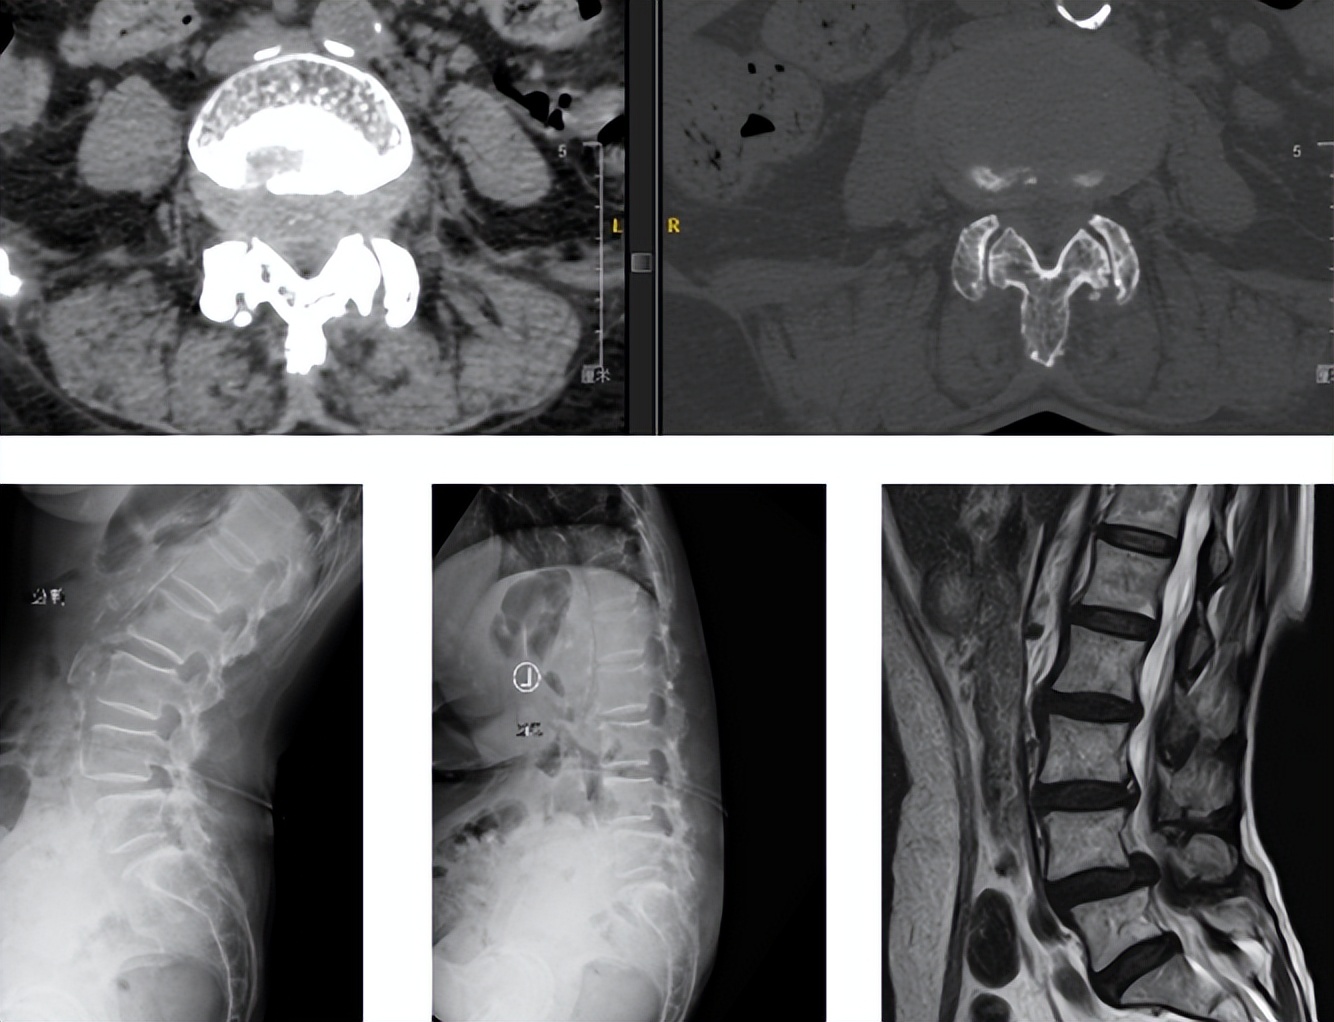

术前资料

入院后,在完善相关检查后王阿姨被诊断为:腰椎管狭窄、腰椎不稳、腰椎间盘突出。随后脊柱外科尚军、张冶手术团队在骨科机器人+3D裸眼显微镜的辅助下,为王阿姨进行了腰椎后路减压+内固定+椎间融合术 (L4/5)。